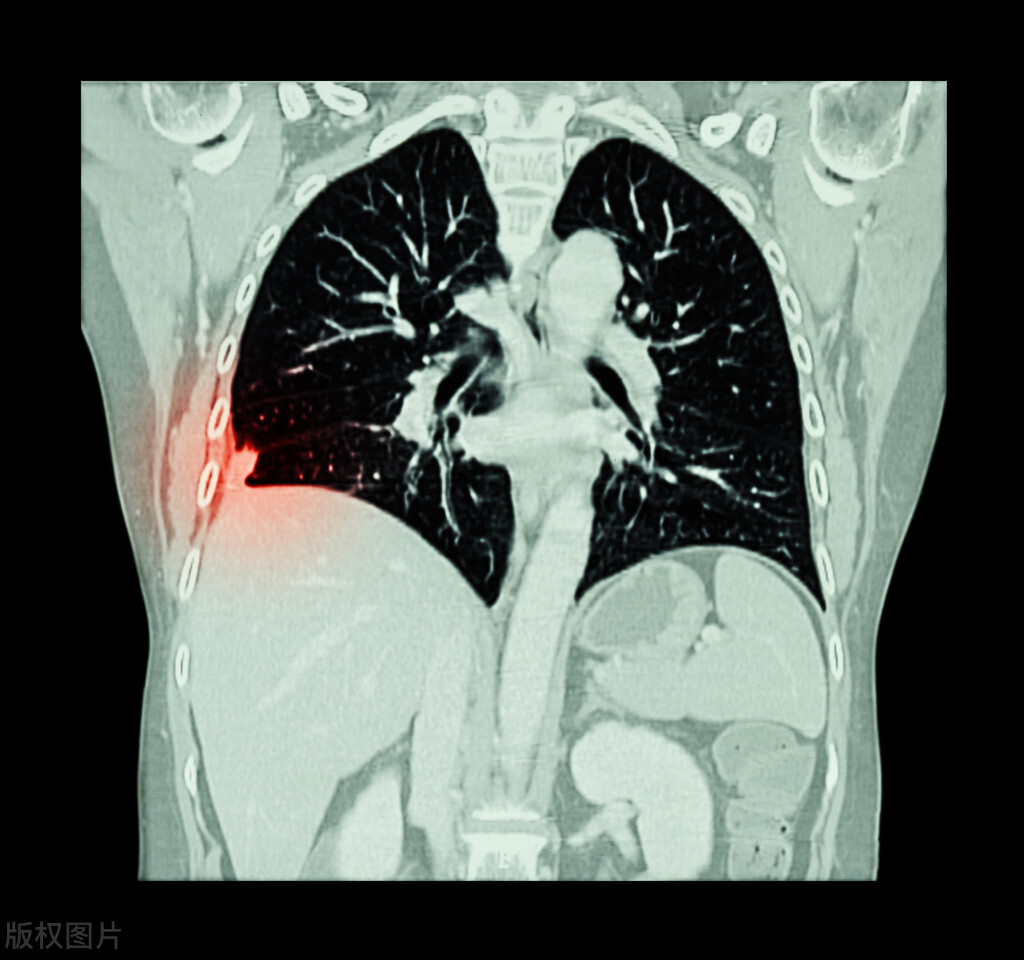

病因学研究发现,吸烟与鳞癌密切相关。像吸烟、大气污染、煤焦油成分及其衍生物、砷的无机化合物、石棉、镉及其化合物、二氧化硅晶体、二氯甲醚、电离辐射等都是公认的肺癌致癌因素。注意了,吸烟和电离辐射 (氡及放射性矿物) 致肺鳞癌的可能性较为肯定。就有学者进行了这样的研究,那就是统计经纤维支气管镜活检明确病理的患者。

结果发现非吸烟者罹患腺癌的比重要大于吸烟者, 吸烟者罹患肺鳞癌的比重要大于非吸烟者, 且吸烟指数越大, 肺鳞癌比重越大。此外,遗传基因有肺癌家族史及既往恶性肿瘤病史、一级亲属被诊断出肺鳞癌的个体,那么患肺鳞癌的风险明显升高。如果罹患肺部慢性基础病,尤其是存在慢性阻塞性肺病、肺结核、间质性肺炎、尘肺等患者,那么肺鳞癌发病率远远高于健康人。

所以,我们其实能做的并不多,在这里我有两点建议。其一是注意引发肺癌的各种诱因,如吸烟、厨房油烟、 电离辐射等。其二就是重视体检,像现在专门有低剂量的CT,辐射比常规DR小很多。如果发现有磨玻璃结节,定期随访,如果在随访过程中增大的比较快或者恶性倾向比较明显,及时至呼吸内科或者胸外科就诊,听从医生的建议,才是正解。